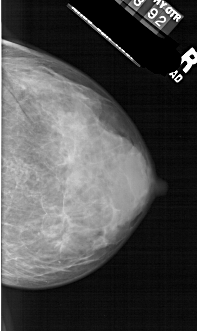

A_1257_1.RIGHT_MLO

RIGHT_CC LINES 5296 PIXELS_PER_LINE 3151 BITS_PER_PIXEL 12 RESOLUTION 43.5 NON_OVERLAY

RIGHT_MLO LINES 6661 PIXELS_PER_LINE 2956 BITS_PER_PIXEL 12 RESOLUTION 43.5 NON_OVERLAY